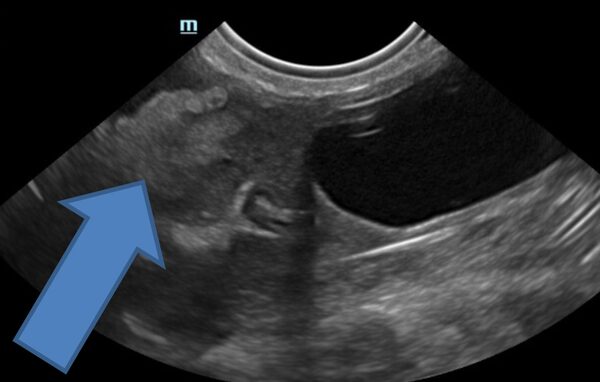

Bei der 9-jährigen Viszla-Mix-Hündin "Gemma" führten wir aus Vorsorgegründen eine Ultraschalluntersuchung des Bauchraums durch.

Zum einen stellten wir einen Herd in der Milz fest und zum anderen eine Nierenzyste links.

Milzherde können gutartige Knoten sein, die aber wie ein Tumor auch aufplatzen und zum Verbluten führen können. Nierenzysten sind bei Hunden glücklicherweise selten. Obwohl sie grundsätzlich gutartig sind können sie durch stetes wachstum das gesunde Nierengewebe verdrängen, zu abflussstörungen des Urins und Schmerzen führen.

Nach sechs Wochen kontrollierten wir, ob die Nierenzyste erfolgreich behandelt wurde und der Ultraschall bestätigte dies.